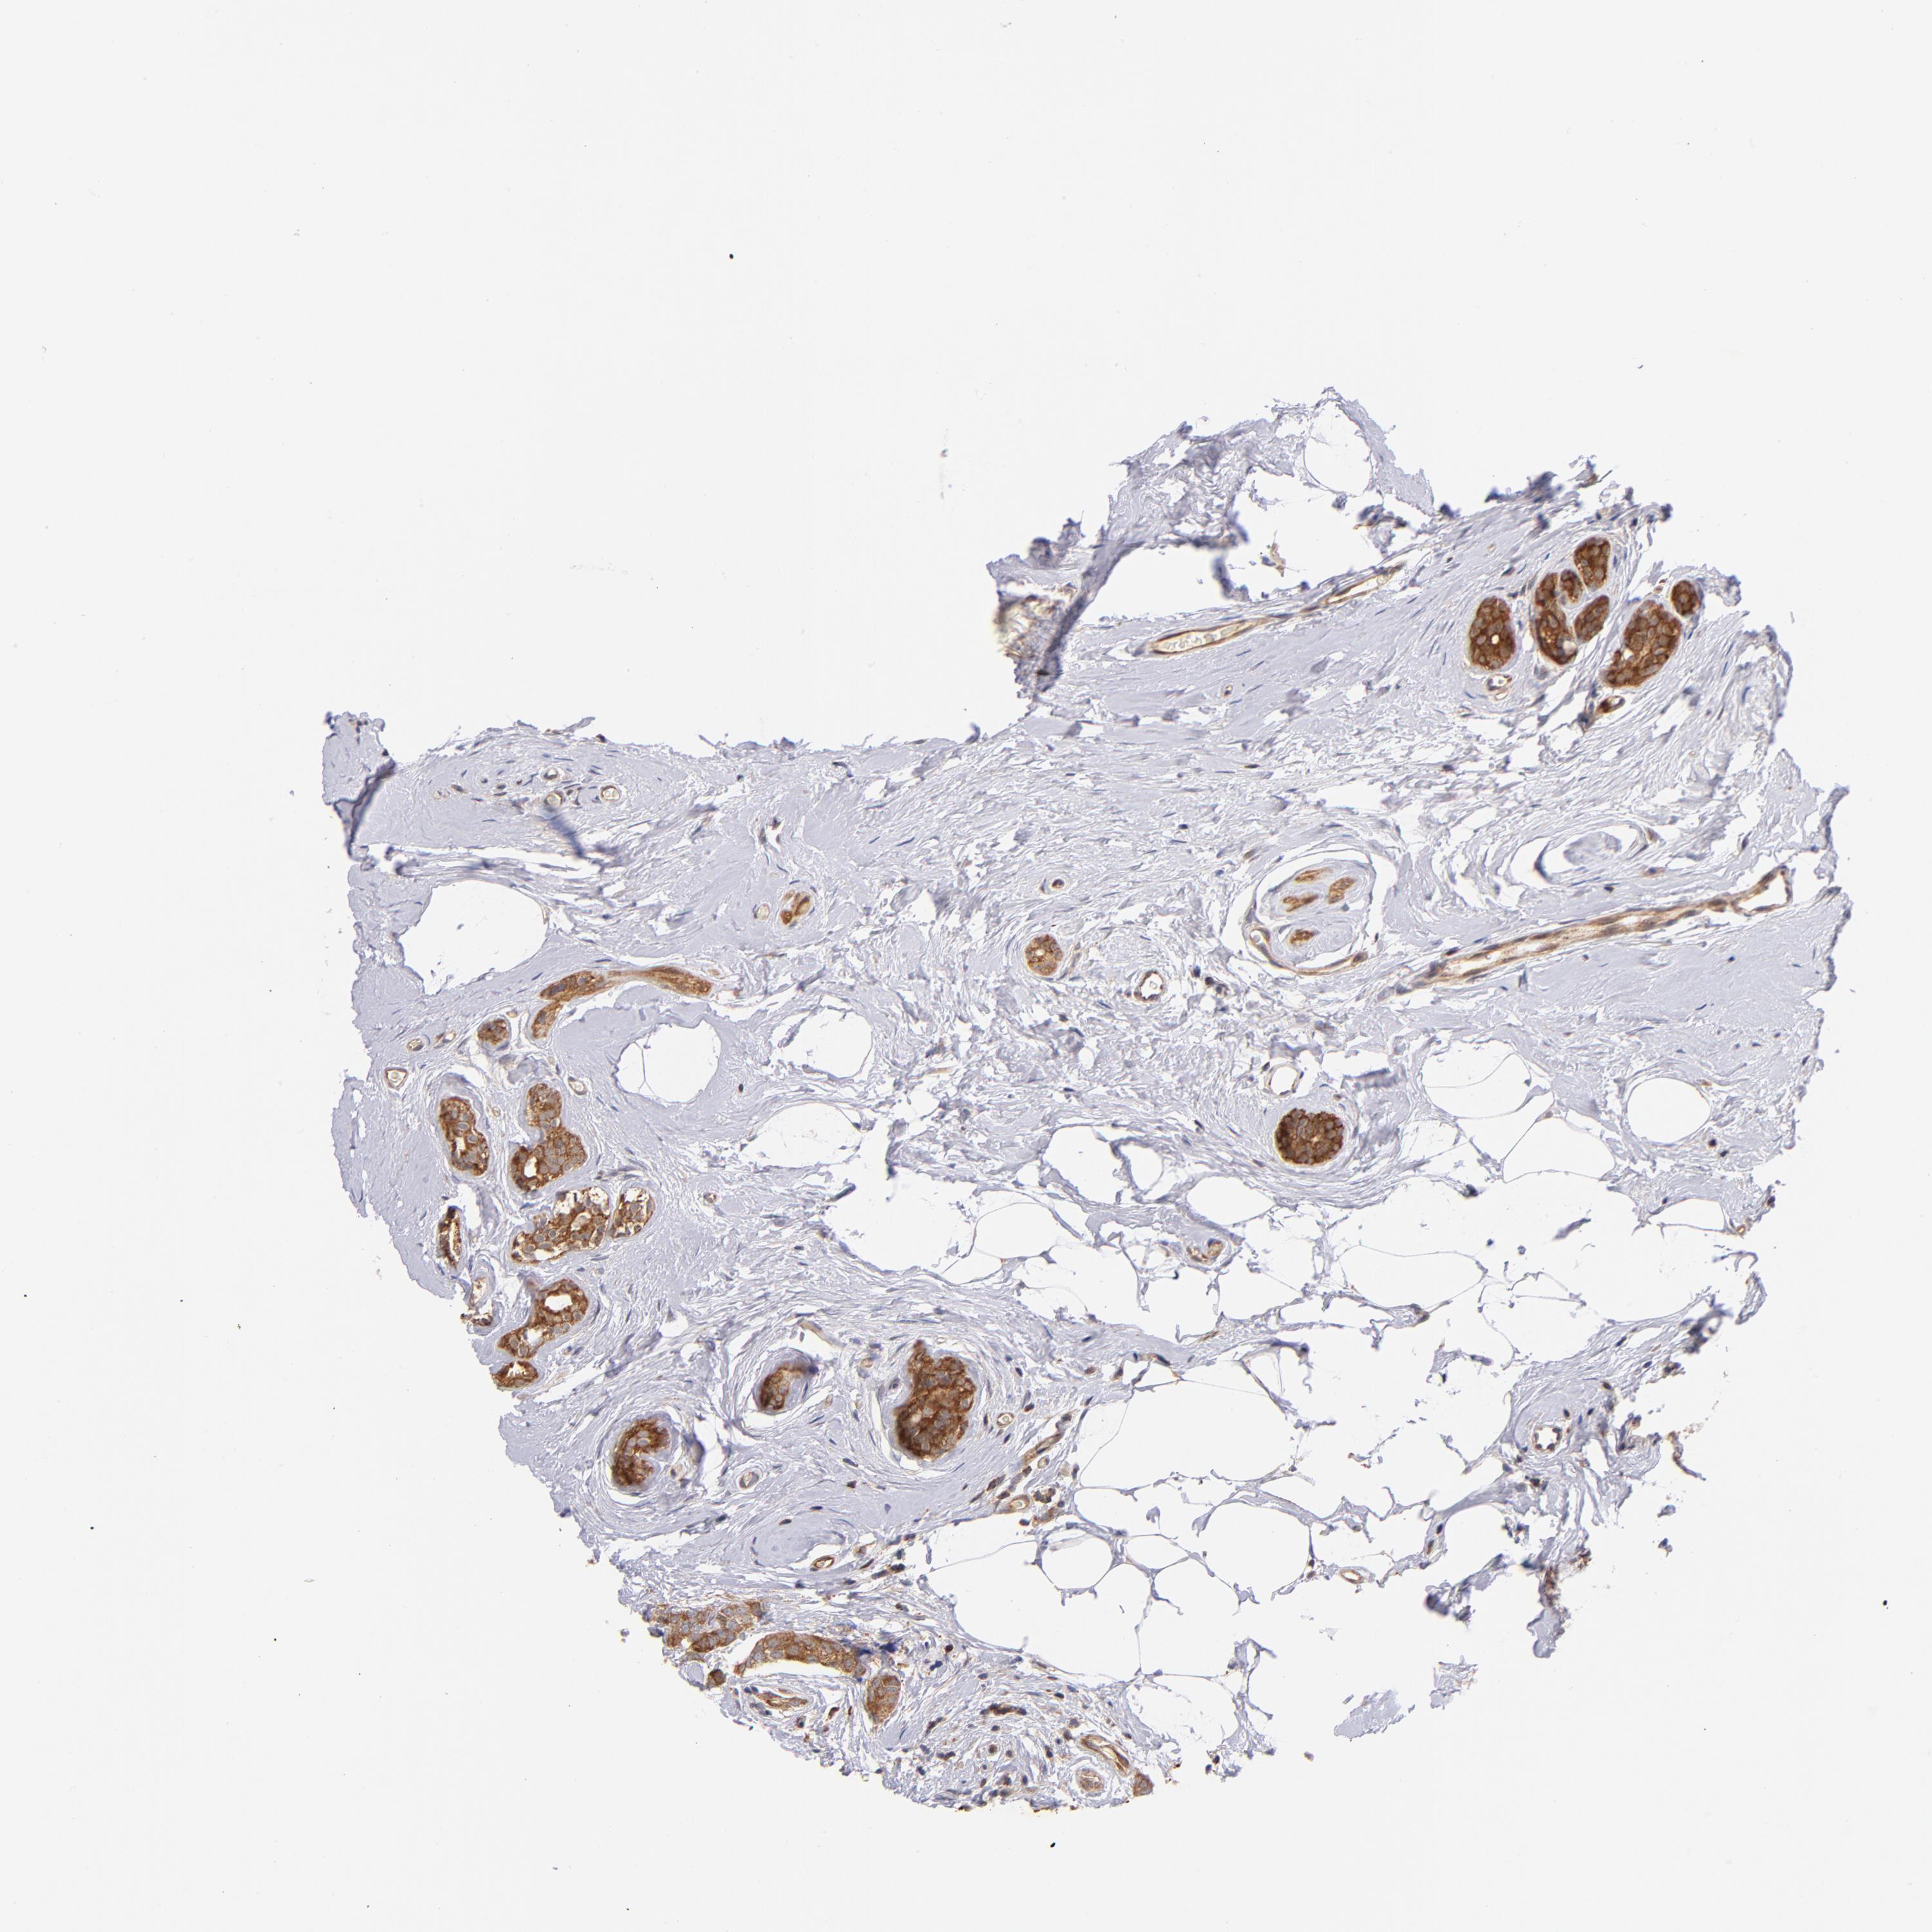

BRCA TCGA BRCA VALIDATION PROTEIN EXPRESSION